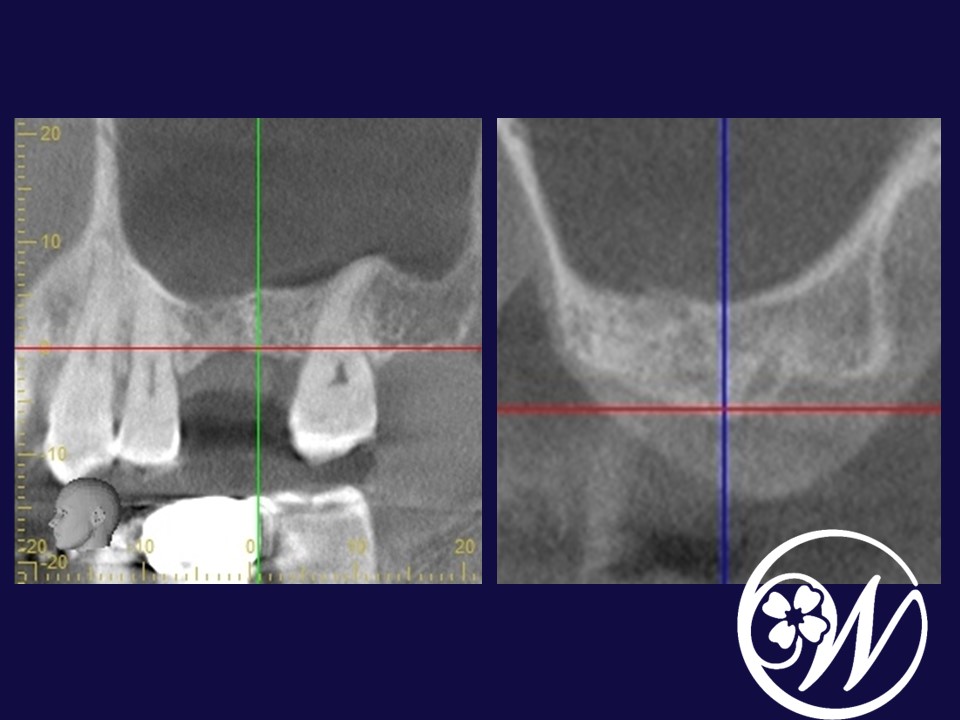

Perfect Sinus Lift - 上顎洞底挙上術のすべて 基礎から学ぶ 歯槽頂アプローチによる上顎洞挙上手術の原理と法則

上顎洞底挙上術に関する専門的な解説書。絶版希少本- タイトル: Perfect Sinus Lift- 著者: 小林 文夫, 高橋 亮男- 出版社: ゼニス出版- 内容: 上顎洞底挙上術に関する詳細な解説- ISBN: 9784897260313裁断してません。ご覧いただきありがとうございます。